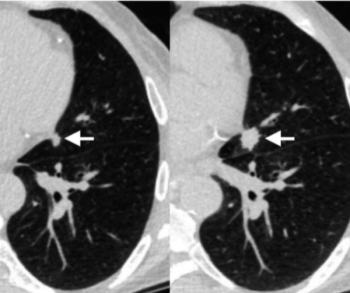

Comparing year-long findings with and without adjunctive artificial intelligence (AI) at a breast cancer screening program in Spain, researchers found the combination of digital breast tomosynthesis and AI had a 92.5 percent accuracy for diagnosing cancer in patients with elevated risk.